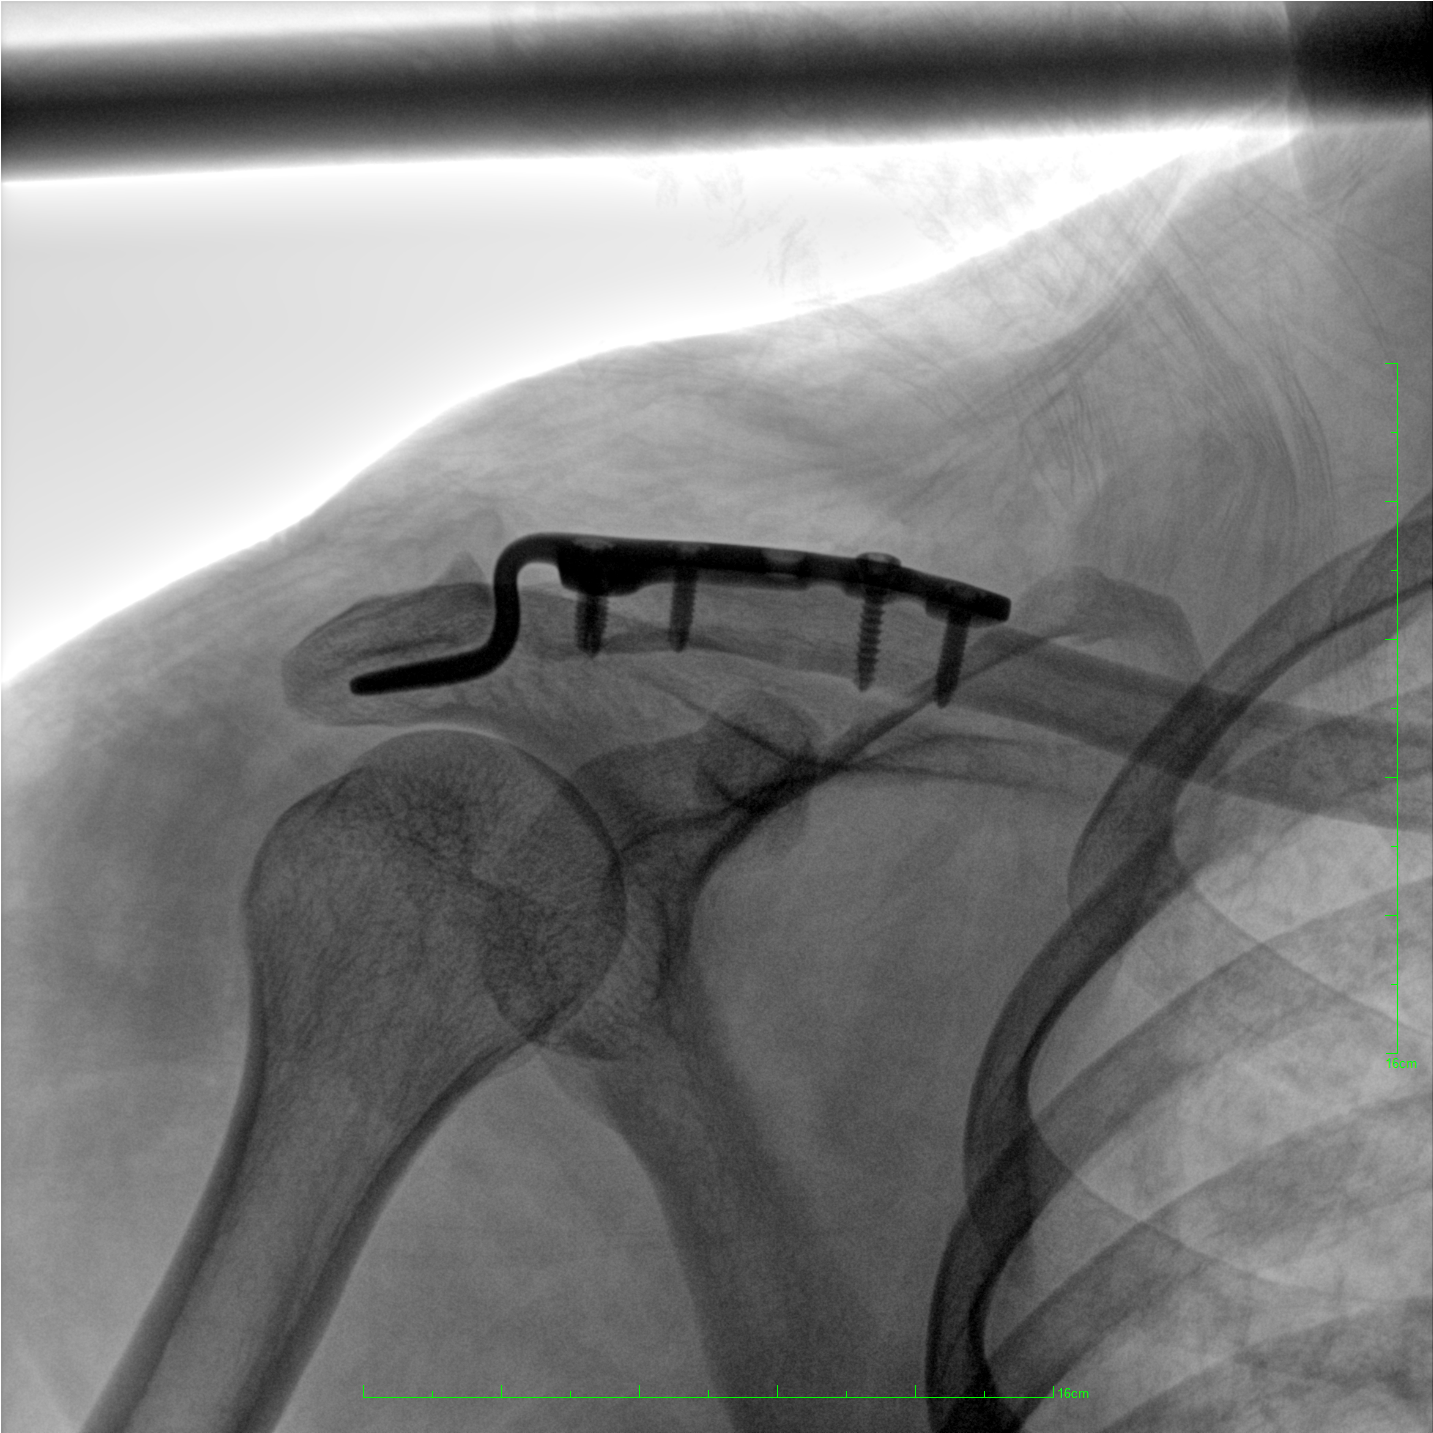

術(shù)中三維成像和橫斷面圖像提供多角度的手術(shù)診斷信息,輔助醫(yī)生進行術(shù)中評估判斷,諸如骨折復位情況和內(nèi)植入螺釘?shù)某叽绾臀恢茫o助手術(shù)更好地完成。